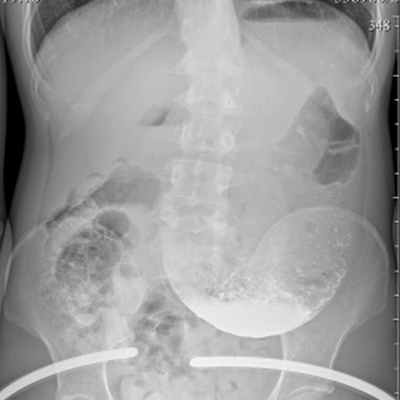

Увеличенный желудок

Подскажите, пожалуйста, насколько это увеличенный желудок?

Из диагнозов - АМК, гастропарез, гипотония желудка

Неудачная дуоденоеюанастомия(такие же снимки и диагнозы были до операции)

Главный симптом - постоянная тошнота

Ещё бывает вздутие, изжога и тд

Даже после жидкости начинается состояние как при отравлении

Об обычной еде речи вообще уже не идёт

- сильно увеличенный, классификация стенозов желудка зависит от времени задержки бариевой взвеси (больше 2 часов, 12, 48, больше 48)

Это снимок через 2 часа и мне давали небольшую нагрузку вместе с барием - 100 грамм хлеба

На след снимках ещё немного бария есть, но желудок уже чуть выше малого таза

То есть он растягивается даже от воды

Во время узи это подтверждено

- нет, он расположен нормально, синус желудка расположен низко

Это последний снимок

Здесь натощак, желудок намного меньше

Скажите, пожалуйста, о чем говорит такое сильное растяжение после еды?

Разница между этим снимком и тот что прикреплён к посту — 17 часов

о чем говорит такое сильное растяжение после еды?

- о нарушениии эвакуации из желудка